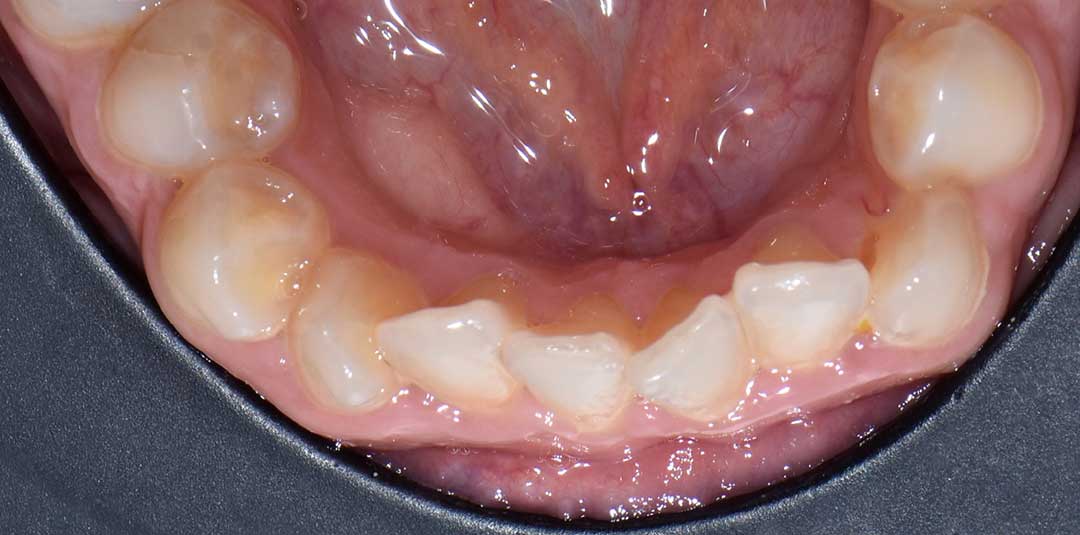

Beautiful Smiles

by Dr. Paolo Bellini